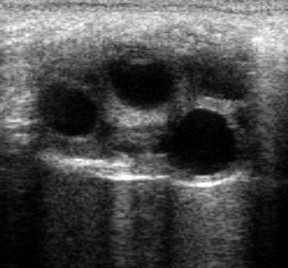

Cel: potwierdzenie ciąży pomiędzy 40. – 120. dniem ciąży. Nie ma zastosowania u osłów

Miejsce syntezy/ Rola fizjologiczna:

produkowana w kubkach endometrialnych – strukturach pochodzenia płodowego, osadzonych w błonie śluzowej macicy klaczy, powstających w wyniku inwazji komórek trofoblastu (zarodka) w endometrium we wczesnej ciąży. Końska gonadotropina kosmówkowa ma aktywność FSH (przeważającą) i LH, co skutkuje powstawaniem tzw. dodatkowych ciałek żółtych u klaczy ok. 40. – 45. dnia ciąży. Mechanizm zabezpiecza utrzymanie odpowiednio wysokiego stężenia progesteronu niezbędnego do utrzymania ciąży, do momentu, kiedy może być ona utrzymana przez progestageny łożyskowe t.j. 100. – 120. dnia ciąży. Sporadycznie, działanie eCG może również pośrednio prowadzić do wystąpienia objawów rujowych u klaczy ciężarnej (eCG prowadzi do wzrostu pęcherzyków jajnikowych, które zwiększają produkcję estradiolu odpowiedzialnego za objawy rujowe).

Kiedy oznaczamy:

podejrzenie/potwierdzenie ciąży między 40. a 120. dniem. W późniejszym okresie kubki endometrialne zanikają.

Pobranie: pomiędzy 40. a 120. dniem po owulacji

Interpretacja: opisowa

Zalety: rutynowe badanie

Ograniczenia: możliwe wyniki fałszywie dodatnie – w przypadku śmierci płodu, jeśli kubki endometrialne nie ulegną regresji (przetrwałe kubki endometrialne) stężenie eCG może utrzymywać wartości wskazujące na ciążę. Opisywane są również przypadki przetrwania kubków endometrialnych powyżej 140. dnia ciąży, ale są to przypadki niezmiernie rzadkie (przypuszczalnie ok. 1 – 2% klaczy)